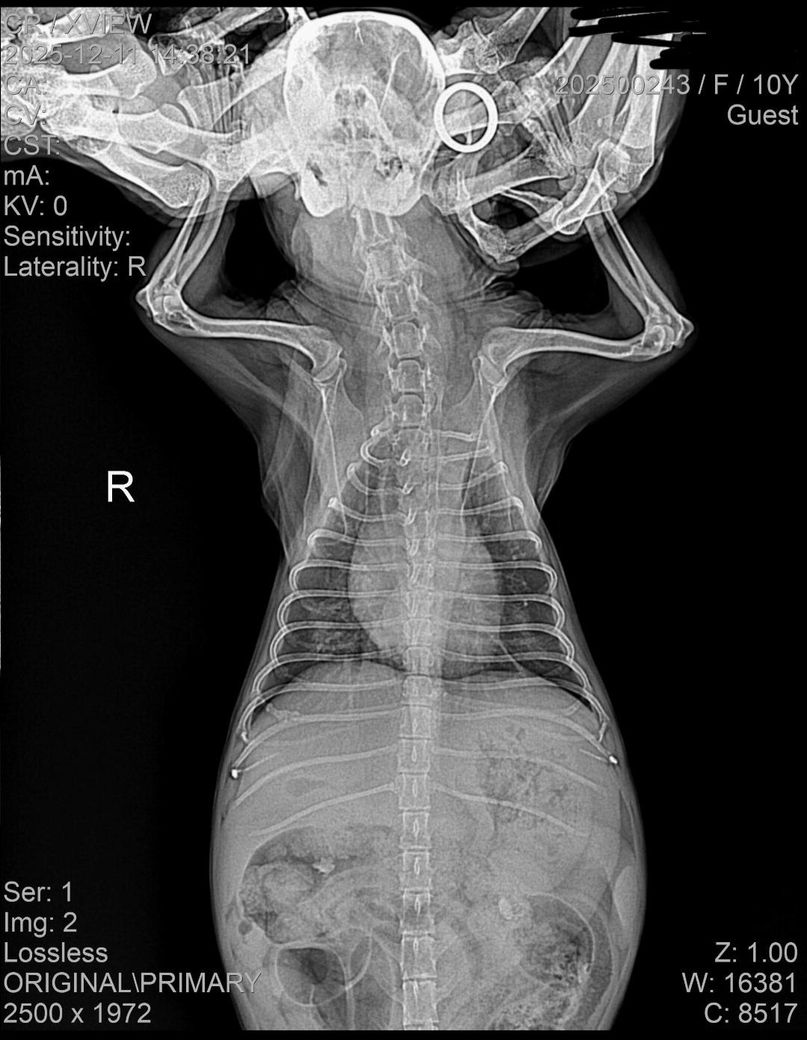

아래 사진은 입원당시 사진입니다.

양측 폐 후엽, 그리고 덧엽에 걸쳐 폐 침윤 양상이 관찰되고 있어 폐수종 가능성이 높은 상태이며, 동시에 폐렴등 이차적인 이상 가능성도 고려해야 하니 주치의의 의견을 따르시기 바랍니다. 폐와 관련된 문제는 시기를 놓치면 다음단계가 질식사이기 때문에 대응은 과도한것이 부족한것보다 언제나 압도적으로 유리합니다.